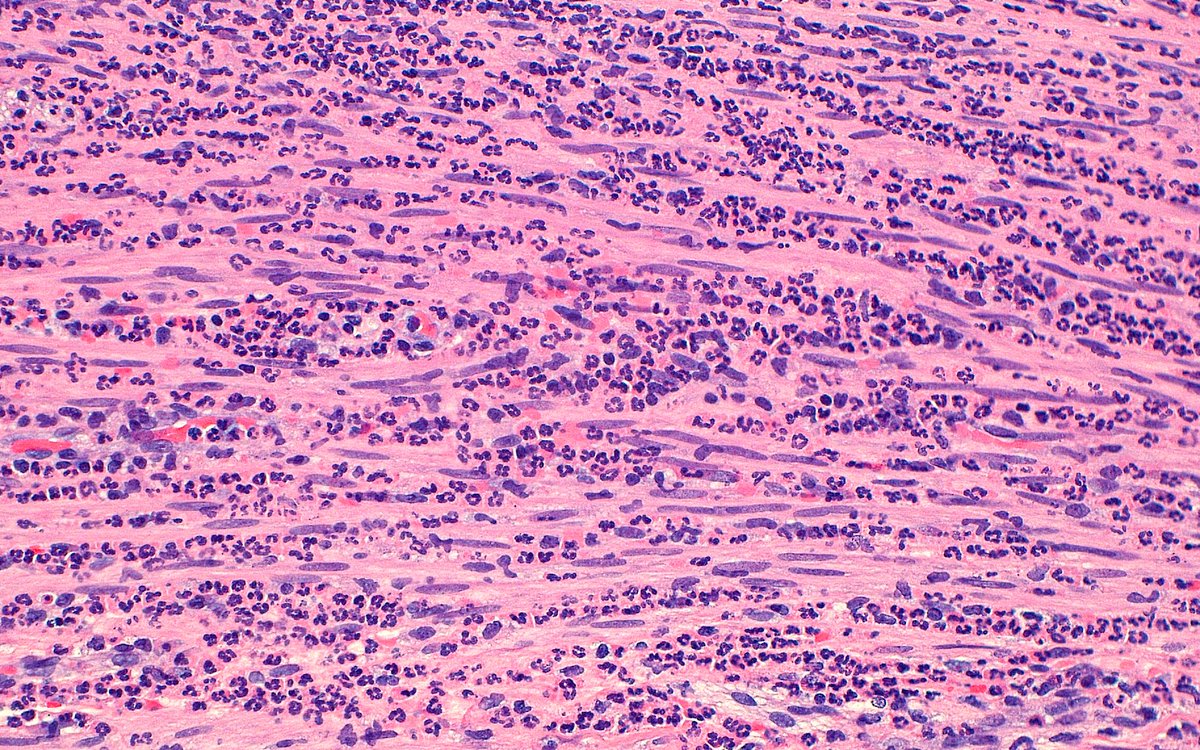

A 45-year-old male with EGPA history and positive p-ANCA showing rare liver involvement. Liver biopsy reveals eosinophilic infiltration. This case highlights how systemic vasculitis can impact any organ. #PathTwitter #Histopathology #EGPA #Vasculitis #EmoryHealthcare